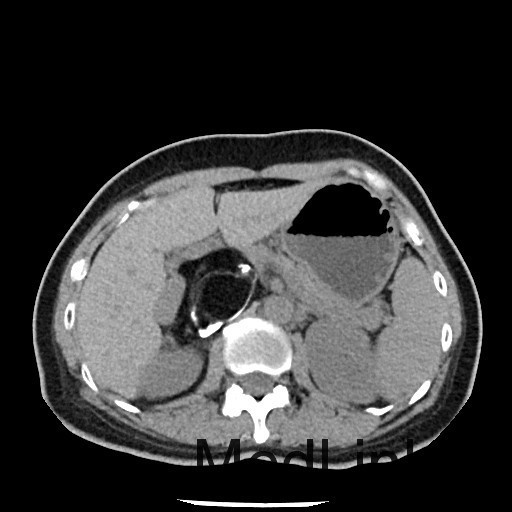

查体:神清,一般情况好,无水牛背、满月脸,皮肤无紫纹。 辅查:全腹CT平扫+增强提示右侧腹膜后区占位性病变,畸胎瘤可能性大。

讨论:本例畸胎瘤因发生在肾上腺区,因此表现为发作性高血压。一般只要在CT图像上看到钙化、脂肪密度等特征性征象,增强扫描实性成分轻度强化,畸胎瘤的诊断一般不难。不过非成熟性的畸胎瘤一般缺少钙化和脂肪成分,此时要与腹膜后其他来源的实性肿瘤相鉴别。本例病理大体能够看到毛发,也是畸胎瘤比较特征性的病理表现。